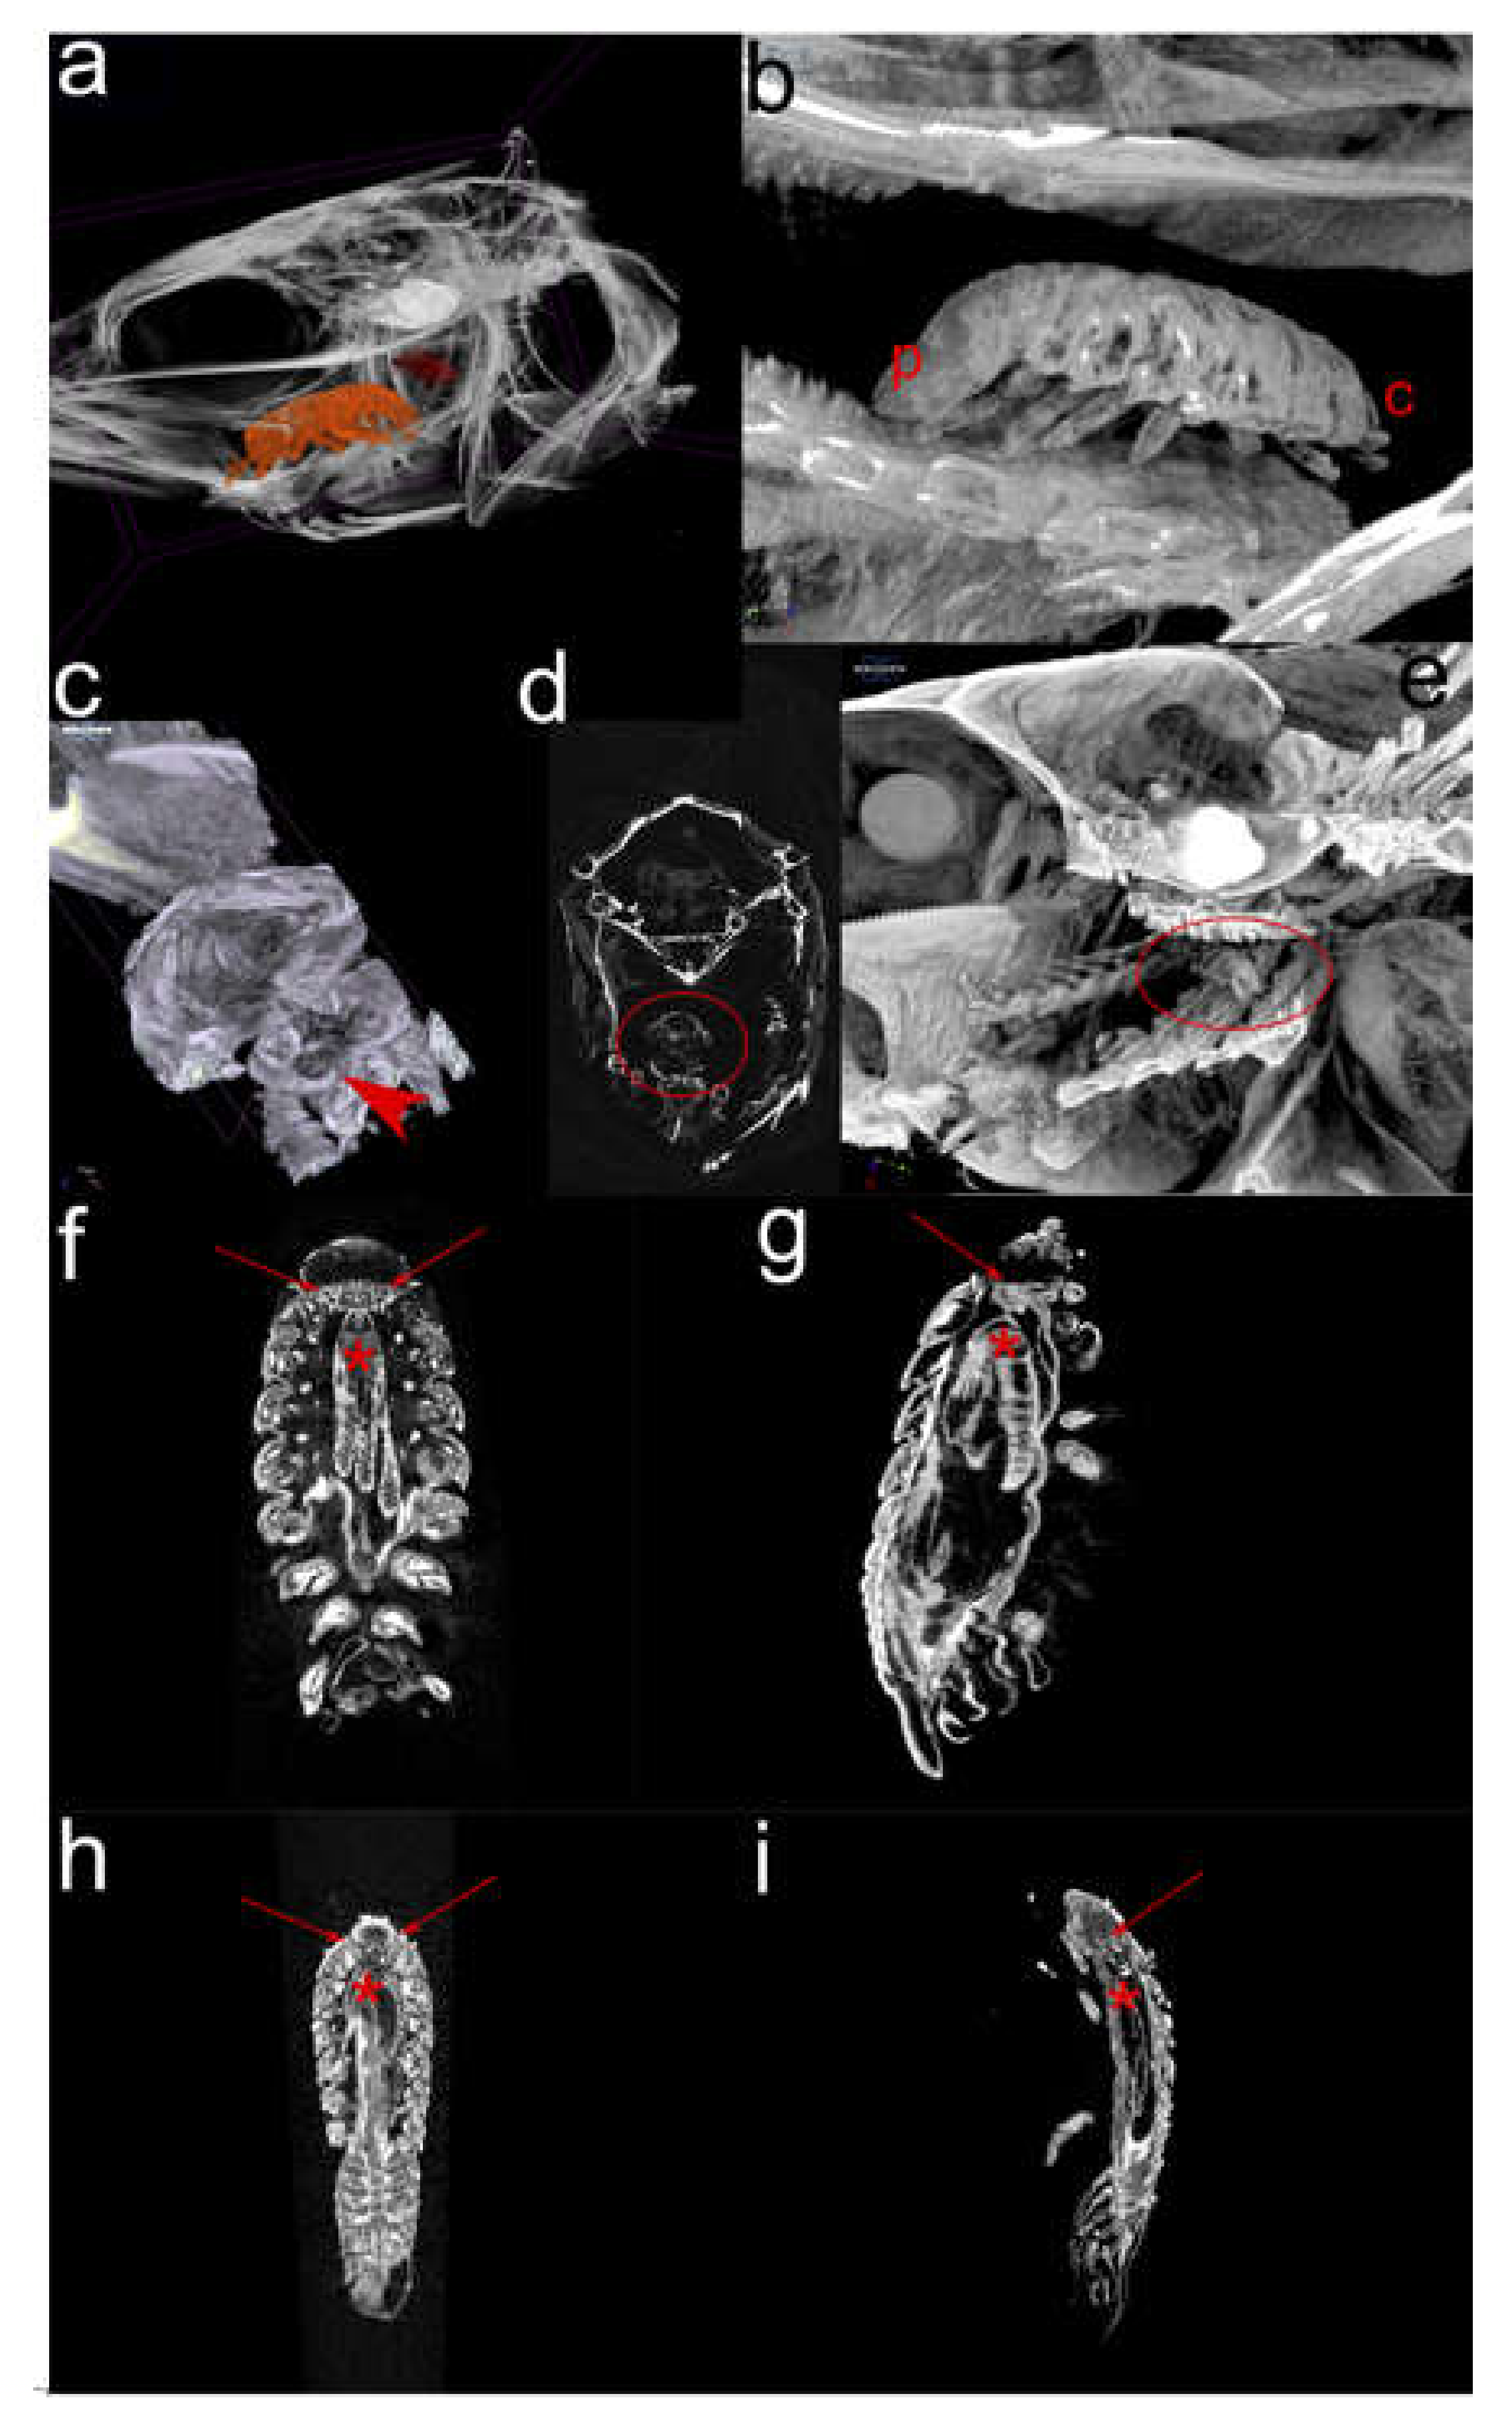

2.2. Micro-computational Tomography (µ-CT) (Figure 3)